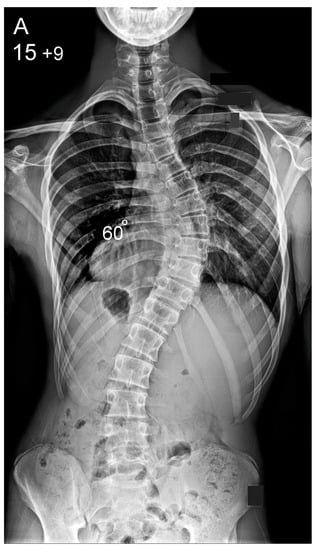

Figure 2.

Patient aged 15 years and 9 months with a right thoracic AIS producing thoracic translocation and listing of the trunk to the right, as well as a lordotic thoracic spine causing spinal penetration into the chest, partial bronchial obstruction and right lower lobe atelectasis (A,B). The patient underwent posterior scoliosis correction using the HS technique which restored segmental and global coronal/sagittal spinal balance at latest follow-up (age 19 years and 2 months) into adult life (C,D). Clinical photographs demonstrate excellent correction of the coronal deformity and associated rib hump after scoliosis surgery (E–H).